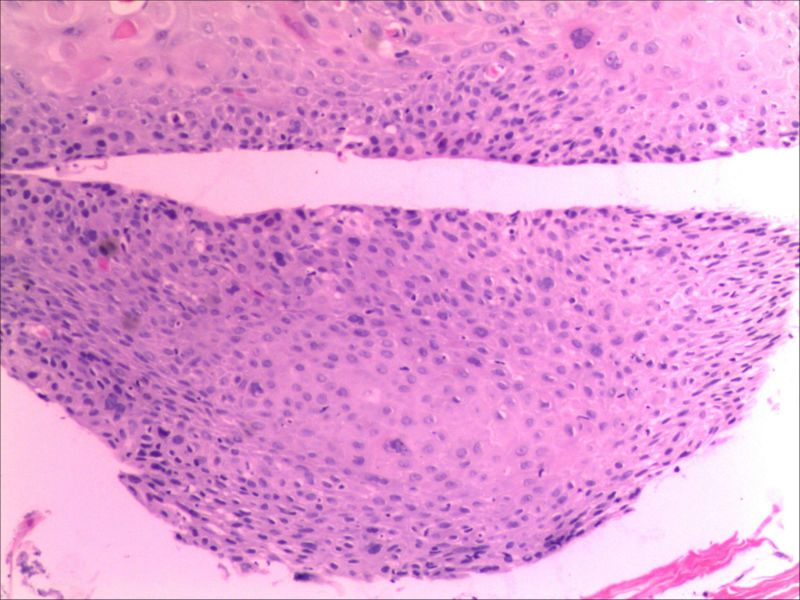

食管活检男64岁食管粗糙

图2